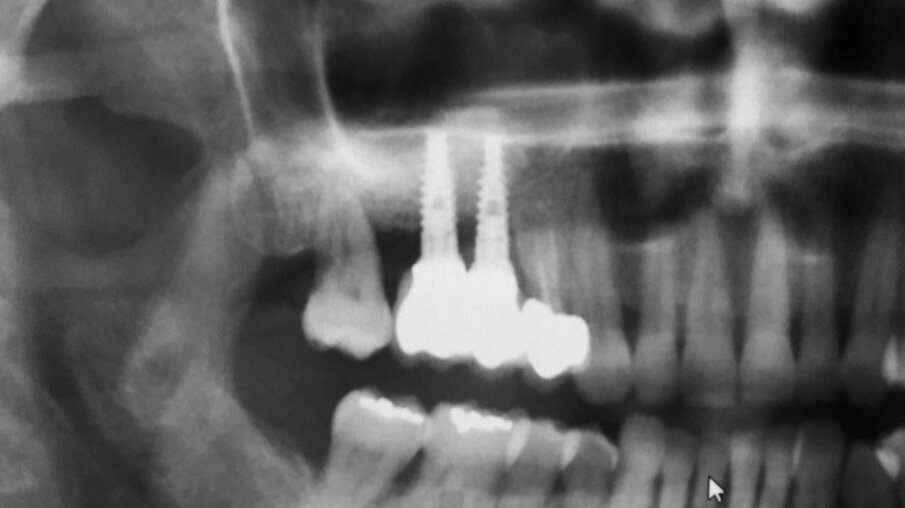

Paziente di sesso femminile, 48 anni, non fumatrice, si rivolge al nostro studio con la richiesta di ripristinare la normale masticazione, ostacolata dall’assenza di due denti precedentemente estratti. L’esame obiettivo evidenzia la mancanza di due elementi dentari nel primo quadrante (1.5 e 1.6). L’anamnesi della paziente è negativa, con un buon livello di igiene e un biotipo gengivale spesso. Viene pertanto prescritta una tomografia computerizzata, CBCT, per valutare il volume di osso disponibile per la riabilitazione (Fig. 1). Analizzando i risultati della CBCT si evince che l’osso basale non è sufficiente a stabilizzare gli impianti necessari per la riabilitazione implanto-protesica e appare ovvia l’esigenza di un aumento dei volumi dello stesso.

Fig. 1_CBCT preoperatoria: si noti la mancanza di osso necessario a stabilizzare due impianti.

Figg. 16, 17_Opt finale e opt di controllo a 14 mesi dal carico.